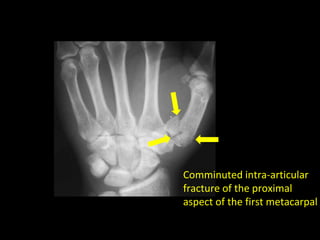

How to describe fractures

• Is the fracture intra-articular?

• Does the fracture line (or one of them if comminuted) involve

an articular surface?

• Intra-articular fractures are associated with a poorer long-term

outcome and can result in secondary osteoarthritis

Comminuted intra-articular

fracture of the proximal

aspect of the first metacarpal